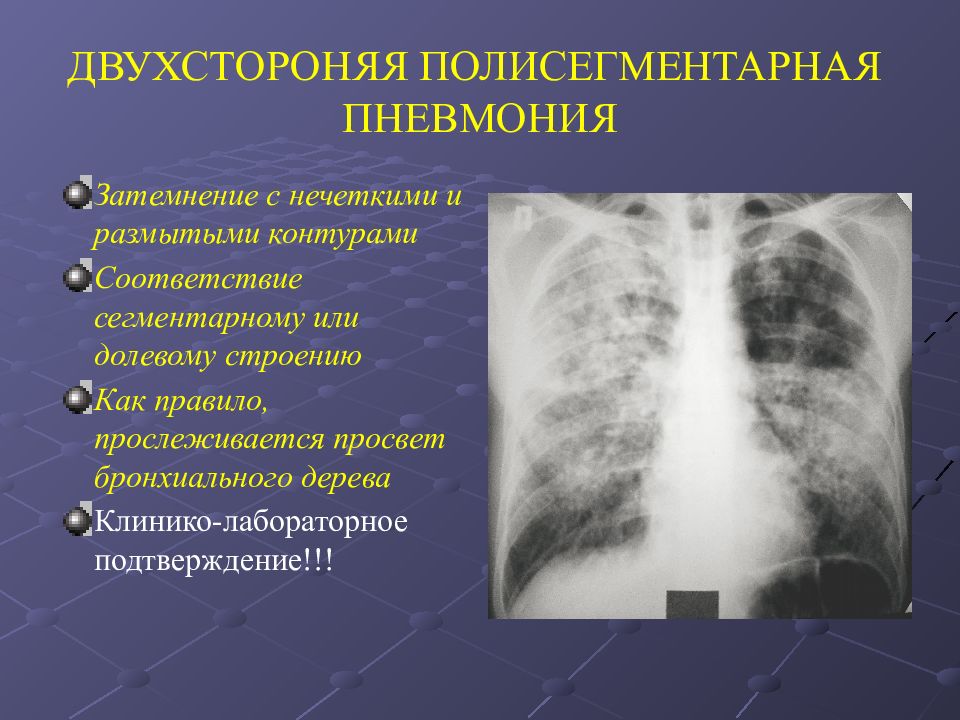

Медицинская тема: легочные осложнения при пневмонии